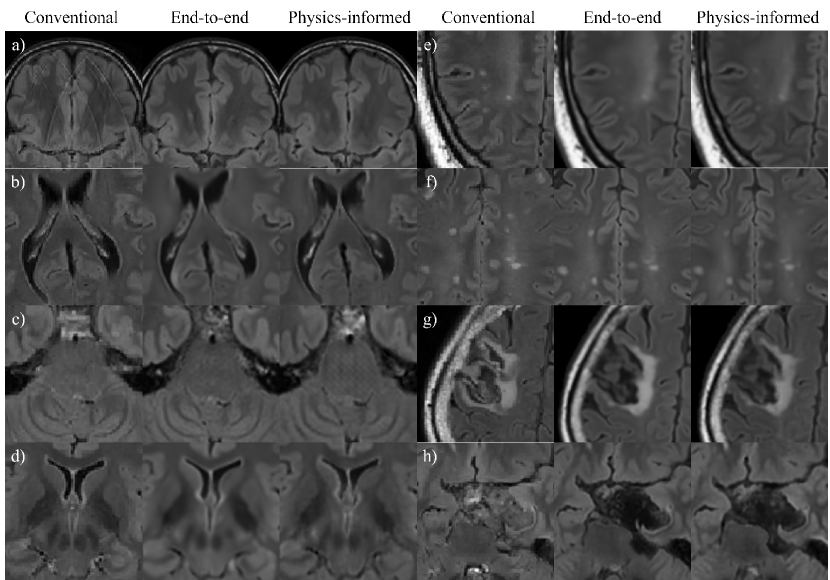

Here, a more detailed analysis of the T2-FLAIR contrasts is provided, where the artifact counts are determined using manual inspection of the images. Motion artifacts were detected for 17 out of 43 test subjects (40%) in the conventional contrasts, which were not observed for the synthMRI of any subject (Fig. 6a). CSF flow artifacts are present for 43 subjects (100%) in the synthMRI (Fig. 6b). Grid-like (chessboard) artifacts were introduced in the brainstem for 23 (53%) and 4 (9%) subjects for the physics-informed and end-to-end approach, respectively (Fig. 6c). Similar chessboard patterns were observed in the parenchyma of 4 (9%) subjects for the physics-informed method. Finally, synthMRI (especially the end-to-end approach) can appear blurrier than the conventional contrasts, for example, the basal ganglia structures (Fig. 6d). This finding has been quantitatively confirmed in a study reported in the supplementary materials investigating image sharpness. Regarding pathologies, both synthMRI methods sometimes miss or result in hypointense lesions with a smaller volume, for example, in epilepsy or multiple sclerosis patients (Fig. 6e-f). Also, more prominent, complicated pathologies such as a stroke can result in inaccuracies. Although the gross shape is captured, hypointensities and blurriness were observed (Fig. 6g). Finally, both synthMRI methods were found to result in an unrealistic suppression of tumor contrast for 4 out of 10 patients (40%) (Fig. 6h).